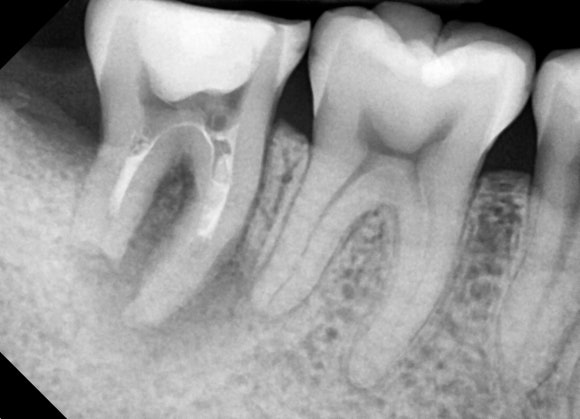

조금 더 확대해서 보겠습니다.

사랑니가 어금니를 밀고 있고,

어금니의 뿌리는 마치 부러진 것처럼 흡수되어 있습니다.

우리 몸의 단단한 조직 - 뼈나 치아-은

염증이 발생했을 때 스스로를 녹이거나

혹은 스스로를 덧붙이는 방식으로

대응합니다.

이 경우엔 녹이는 방향입니다.